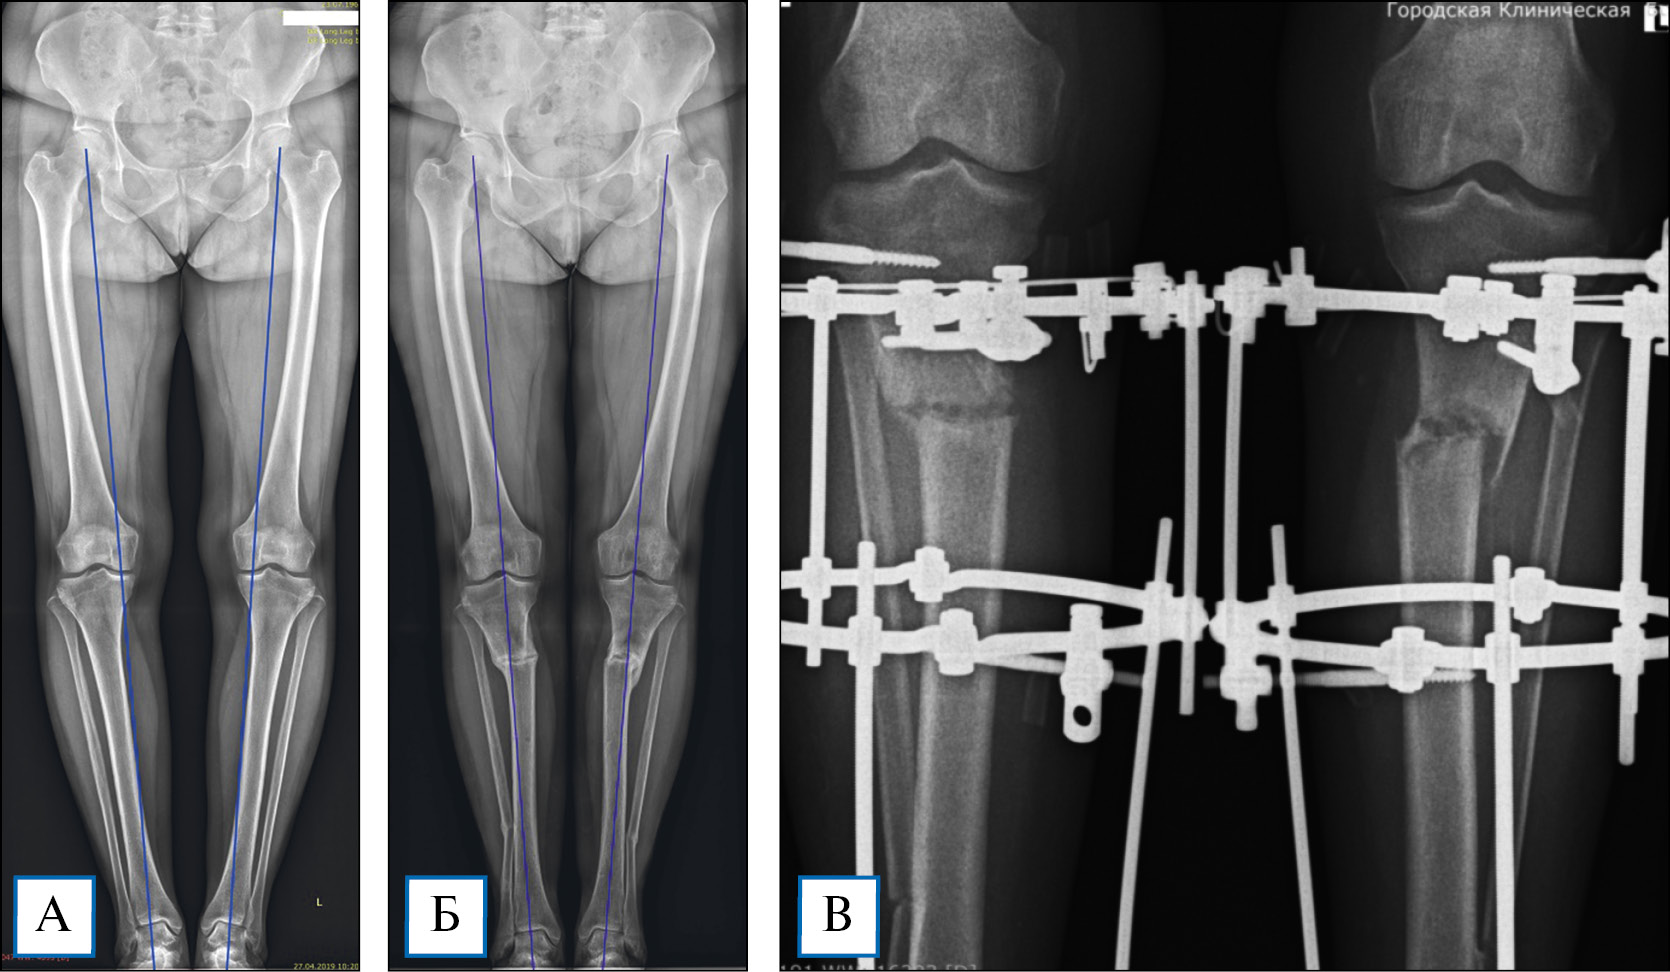

Рис. 1. Рентгенография нижних конечностей по всей длине в прямой проекции

Примечание. А, Б — положение пациента в процессе исследования; В — рентгенограмма нижних конечностей по всей длине, определение положения механических осей с обеих сторон и разницы длины ног (разная длина ног в данном случае — впервые выявленная находка); Г — рентгенография левой голени (фрагмент длинномерного изображения) с определением mMPTA.

- в прямой (переднезадней) проекции пациент стоит в расслабленном положении, колени полностью разогнуты, стопы едва касаются друг друга, надколенники ориентированы кпереди (рис. 1);

- в боковой проекции пациент стоит таким образом, чтобы колени были максимально разогнуты, а стопы располагались друг за другом на одной линии (рис. 2);

- при клинически диагностированной разнице в длине ног под укороченную конечность необходимо подкладывать подставку, адекватно компенсирующую величину укорочения.